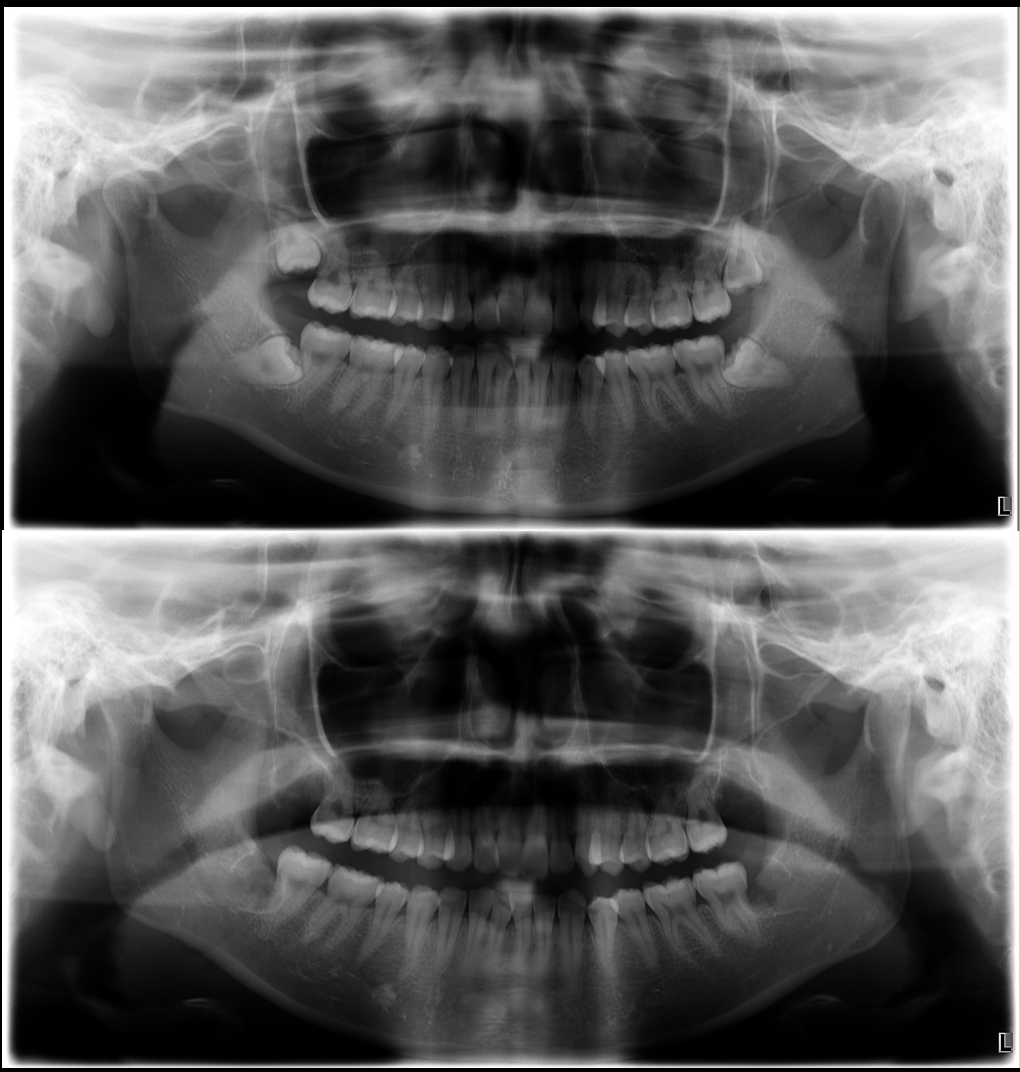

CT撮影によって、親知らずの位置や神経との距離、骨の状態を3次元的に把握。

これにより、安全で最小限の侵襲で済む術式を事前に計画します。

親知らずが腫れて痛いということで当院受診

最小限の侵襲で、粘膜の挫滅や出血が抑えられるように抜歯

根尖が複雑に湾曲しており、骨を掴んでいた